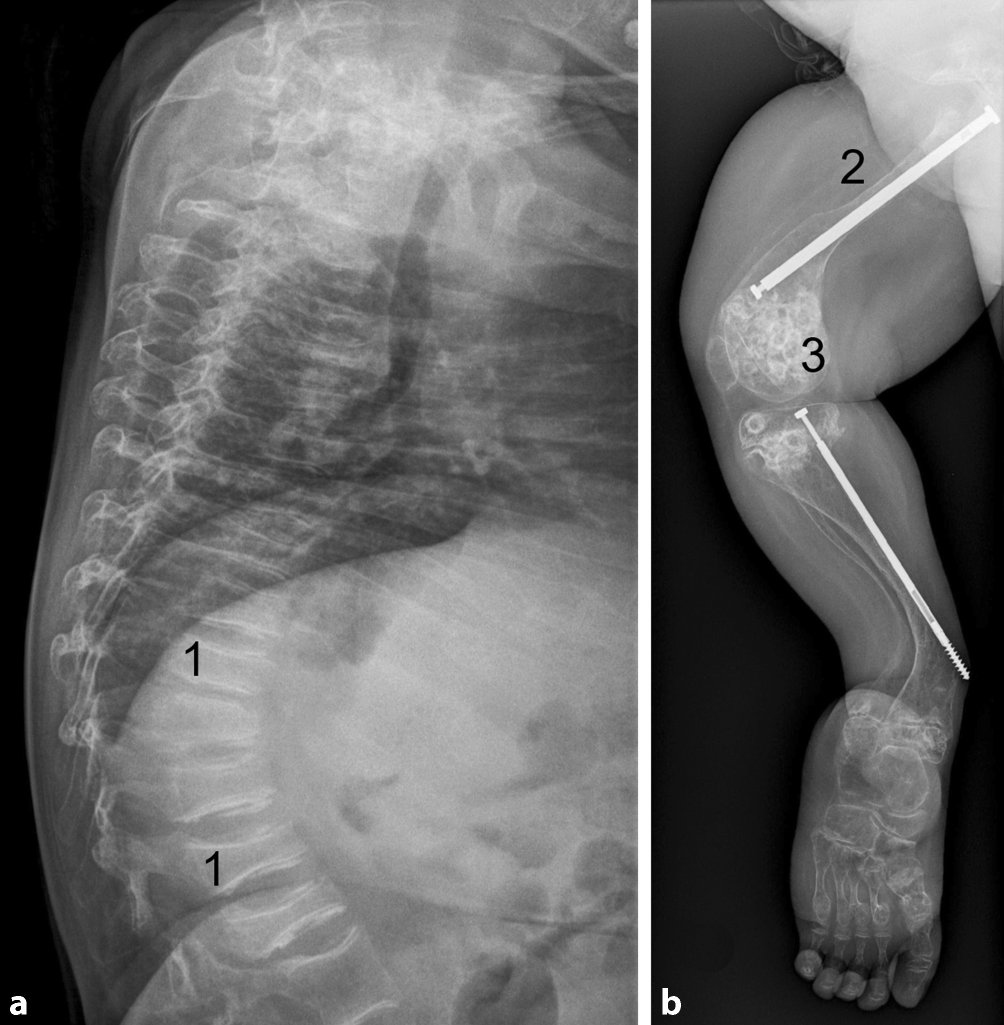

Zur Abklärung von Frakturen steht die Röntgenuntersuchung an vorderster Stelle. Die langen Röhrenknochen können Deformierungen aufweisen, die Kortikalis ist meist dünn und der gesamte Knochen erscheint auf der konventionellen Röntgenaufnahme osteopen. Die Röntgenaufnahme einer seitlichen Wirbelsäule (Lenden- und Brustwirbelsäule) ist unverzichtbar, um nach Kompressionsfrakturen oder Deformierungen (Fisch- oder Keilwirbelkörper) zu suchen, die ein starkes Indiz für eine reduzierte Knochenstabilität sind (s. Abb. 1a). Die metaphysären Bereiche können aufgetrieben sein und durch versprengtes Knorpelgewebe kann es zu den sog. „Popcorn-Metaphysen“ kommen (s. Abb. 1b).

Röntgenaufnahme der lateralen Wirbelsäule (a) einer Patientin mit einer schweren Verlaufsform einer Osteogenesis imperfecta , verursacht durch eine qualitative Störung in COL1A2. Es sind ausgeprägte Wirbelkörperveränderungen (z. B. 1, unauffälliger Wirbelkörper hat 2:3- bis 4:5-Verhältnis von Höhe zu Breite) zu sehen. Aufnahme eines Beines der gleichen Patientin mit Z. n. operativer Frakturversorgung und Begradigung mit einem Teleskopnagel (2) mit typischer dünner Kortikalis und Auftreibung der Epiphysen mit eingesprengten Knorpelfragmenten, die zum Bild der Popcorn-Epiphysen (3) führt. Die Verankerung des Nagels in der distalen Unterschenkelepiphyse scheint in der vorliegende Ebene nicht mehr gegeben und somit nicht optimal (b).